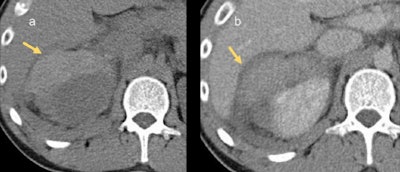

In cases of renal trauma, the imaging protocol used should adequately assess three key components of the kidney: the parenchyma, vasculature, and collecting system.

"Imaging usually occurs in the setting of general abdominal trauma for which a trauma protocol is employed to assess for a wide range of injuries," Bambrick and colleagues continued. "A trauma protocol for the abdomen involves portal venous-phase imaging, which corresponds with the corticomedullary phase, thus enabling assessment of renal parenchyma. There is also an increasing tendency to include an arterial phase in the trauma protocol to assess for arterial injury."